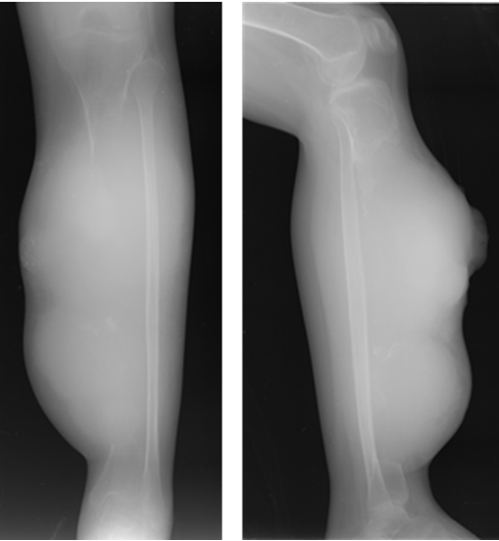

A 35-year-old Indonesian mongoloid female patient presented with a painful lump in her left leg. She had history of lump in her left leg since seven years prior to admission. Initially, the lump was only 1 cm in diameter. There was no history of trauma. The patient was initially treated by general surgeon, and had undergone excision of the lump. After the surgery, recurrence occurred and the lump developed gradually. Within seven years, the patient did not routinely visit hospital to have the condition of the lump checked. One week prior to admission, the patient complained about difficulty in breathing. She came to a primary hospital and was found to have a pleural effusion in her right lung and chest tube was inserted. She was then referred to our hospital. On the physical examination, a 10x10x5 cm hard tender mass was found in the left lower leg (Figure 1). Range of movement (ROM) in the left knee joint was full, but in the ankle joint, the ROM was limited. Laboratory results including tumor marker were unremarkable. Plain radiograph of the left leg showed lytic lesion in diaphysis and metaphysis of the left tibia with osteodestruction of tibia and extension to the surrounding soft tissue (Figure 2). A chest radiograph was performed (Figure 3) which showed bullae in the superior lobe of the right lung, pneumothorax, fibroatelectasis in the middle lobe of the right lung, and right pleural effusion. A chest MSCT showed hydropneumothorax and multiple bullae of the right lung and solitary nodule in the left lung suspected to be a distant metastasis from the primary tumor site (Figure 4). The patient was assessed with hydropneumothorax of the right lung caused by possible malignancy. A fine needle aspiration biopsy (FNAB) of the lesion in the left leg then performed with the result of clustered tumor cells within a group, with small cells with atypia, small amount of cytoplasm, spindle nucleus with hyperchromasia with background of lymphocyte and erythrocyte (Figure 5). A clinicopathological conference was then arranged with a recommendation of transfemoral amputation. A transfemoral amputation was then performed and the histopathological result showed a pattern of epithelial tumor with solid arrangement and infiltration to surrounding tissue, including to the upper dermis. The observation of the cells showed small to moderate cell sizes, small amount of cytoplasm, round to spindle nucleus with small amount of mitosis. The conclusion of the histopathological examination was islands of epithelial cells in a densely-populated stroma of spindle cells suggesting adamantinoma (Figure 6). The positive cytokeratin was found in the immunohistochemistry on the tumor cells and it was also relevant with the diagnosis of adamantinoma (Figure 7). | ||||||

The symptoms initially present with nonspecific characteristics and its variety of the symptoms is related to location and extent of the disease. Pain is the most common clinical manifestation reported. It was in accordance to this case where the patient was presented with painful lump on her left lower leg. The onset of the clinical sign and symptom is insidious with slow and progressive characteristic. The patient usually tolerates symptoms for many years before seeking medical attention because of this characteristic of clinical manifestation as seen in this patient [5]. However, some of the patients present with swelling with or without pain as local swelling being the second most common symptom to appear. In addition, this case also showed that involvement of the anterior tibial surface can produce bowing of the tibia [6]. Based on radiographic assessment, adamantinoma is an osteolytic type with mono or multi-loculated lesions. In accordance to its benign characteristics, it is well circumscribed with septa and a peripheral condensation may appear. It is usually appear in the diaphysis or metaphysis of the anterior tibial. The lesion usually grows intracortical and it may spread longitudinally. However, it does not rule out the possibility of cortex destruction and marrow cavity invasion of the tumor [7]. The MSCT examination could reveal the characteristics of the lesion better than plain radiograph and can also detect another tumor site invisible on plain radiographs. The differential diagnosis based on plain radiograph examination including fibrous dysplasia and osteofibrous dysplasia [2]. . The patient in this case had tumor in her left leg which develops progressively after the first excision seven years ago. This might be due to inadequate attempts of removal where incomplete resection may result in higher recurrence rate up to 30% in the period of 85 months. Therefore, adamantinoma is suggested to be treated with wide surgical excision and reconstruction or amputation since its likelihood of healing is high subsequent to radical treatment [2] [3]. If early diagnosis is successfully made, wide local excision with a substantial margin of normal bone is still acceptable [8]. However, if there has been more than one recurrence or in large tumor with extension to the surrounding soft tissues, radical resection or amputation is advisable as shown in this patient where knee amputation was performed [9]. Adamantinoma is a low-grade malignant tumor of epithelial origin which metastasizes late. This tumor is insensitive to radiation and has capabilities of metastasis, especially to the lung. [8]. Metastases including in lung or lymph nodes are rare and can occur in 10–20% of patients. Pulmonary metastases are more common that regional nodal metastases from this tumor. It is not uncommon to develop distant metastases even up to 10 years after detection of the primary [3] [5]. This was in accordance with this case, where the main reason to seek medical management was due to difficulty in breathing and it was correlated with repeated local recurrences that might be due to inadequate primary excision of the tumor. However, it is difficult to evaluate its true metastatic potential due to several reasons such as long term follow-up, low number of the case, and slow growing nature of the tumor [5]. Several reports in literature have described metastasectomy for pulmonary lesions in both curative and palliative settings with good results. Mean survival of patients with metastatic disease is reported to be 12 years. There appears to be no definitive role for radiotherapy or chemotherapy [10]. Due to its excellent prognosis, it is crucial to diagnose this rare bone tumor in the early stage. It can be achieved by histologic examination, where this tumor can be distinguished easily. However, not only this tumor is rare, the heterogeneity of the tumor presentation may lead to confusion in some cases. On the histologic examination with inadequate sample taking, epithelial component may be seen only focally in the differentiated adamantinoma case, therefore in some cases, extensive sampling of the tumor is mandatory [11]. The challenge in making diagnosis and preparing proper management emphasizes that clinicopathological conference among orthopedic surgeon, pathologist, and radiologist was very important to ensure the patient get the best treatment available in musculoskeletal tumor cases. At the moment where the diagnosis is certain, resection with wide surgical margins or amputation can be applied to the patient.. | ||||||